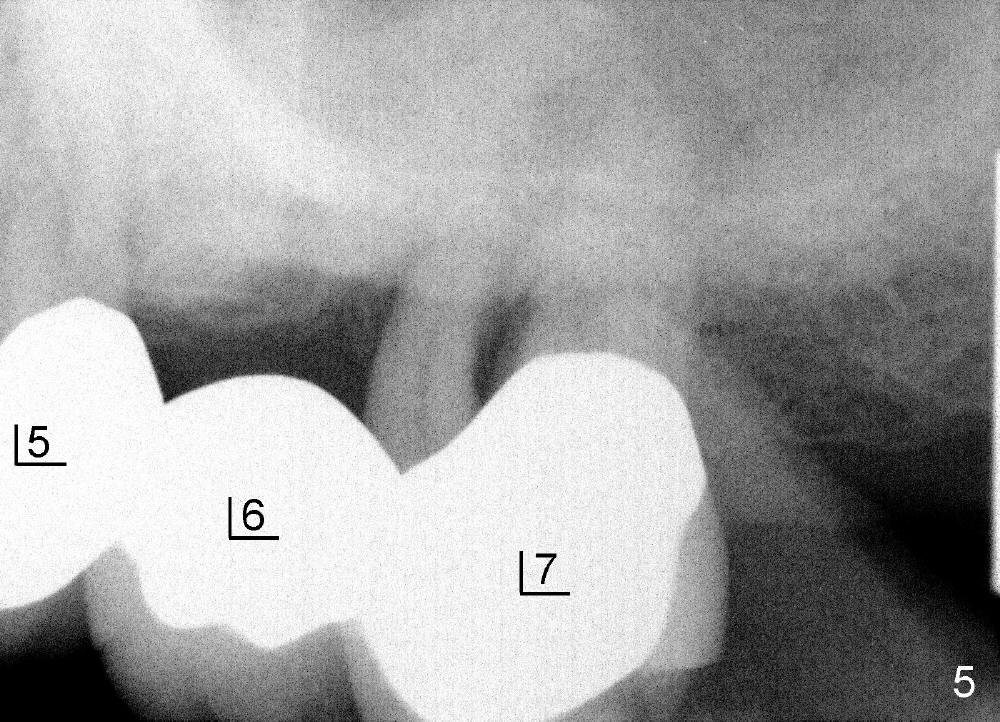

五十来岁郑先生有两个主诉:第一,左上桥松动(图二,五),要求拔除后面基牙;第二,右下六号牙处需要植牙(图三)。初步检查几张根尖片(图一至五),他是典型牙周病病人,悲观人认为不治之症,乐观人却认为这是最好植牙病例,虽然骨质吸收严重,但是剩下骨质坚硬,因为牙周病病人往往咬合力很大。充分利用剩余骨质吧。现在他口腔卫生不差。

病人要求先处理左上桥(图二,五),我们准备在五六号牙之间切断桥(图六:黑线),拔除七号牙,立刻植牙。那里骨头高度多少?是黑线,还是红线?一两天我们就会给您答复。估计在那里可以植入七或者八乘十一或者十四毫米植牙。

如果时间允许,我们可能同时在左上六号牙处植牙,骨头高度好像不乐观(图五,六),积极人在图二找骨头,估计可以植入六乘十一或者十四毫米植牙。